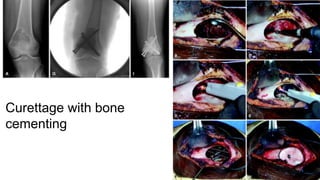

● FOR DEFECTS AFTER RESECTION OR CURETTAGE,EITHER

ALLOGRAFT OR BONE CEMENT USED AS FILLING AGENTS

•THE ABOVE DISADVANTAGES OVERCOME BY USE OF BONE

CEMENT

•PROVIDES IMMEDIATE STABILITY-HENCE QUICKER

REHABILITATION

•EASIER DETECTION OF RECURRENCE SEEN AS EXPANDING

RADIOLUCENCY ADJ TO CEMENT

•KILLS RESIDUAL TMR CELLS THROUGH POLYMERISATION HEAT.

● CYTOTOXIC AGENTS- METHOTREXATE AND ADRIAMYCIN CAN BE

INCORPORATED IN BONE CEMENT.

Curettage with bone

cementing